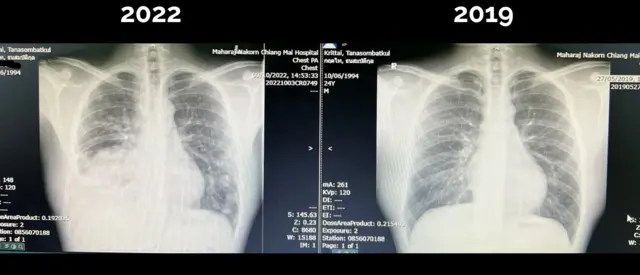

อ.นพ. กฤตไท เผยแพร่ภาพการเอกซเรย์ปอดเมื่อปี 2562 หรือเมื่อ 3 ปีก่อน แสดงให้เห็นว่า แทบไม่มีอะไรผิดปกติ

ภาพเอกซเรย์ล่าสุด แสดงให้เห็นว่า ปอดด้านขวาของ อ.นพ. กฤตไท หายไปครึ่งหนึ่ง “มีก้อนขนาดใหญ่ถึง 8 ซม. และมีน้ำในปอดร่วมด้วย” ไม่เพียงเท่านั้นยังเห็นสัญญาณการกระจายของเซลล์มะเร็ง เพราะพบก้อนเล็ก ๆ ในปอดซ้ายอีกหลายก้อน

เขาระบุว่า ถ้าสภาพปอดเป็นเช่นนี้ น่าจะเหนื่อยเวลานั่งคุย และสอนหนังสือ แต่อันที่จริง วันก่อนจะเอกซเรย์ เขายังไปเล่นบาสเก็ตบอลในระดับการแข่งขันกีฬาได้ แม้จะยอมรับว่า ความ “ฟิต” ช่วงหนึ่งเดือนก่อนหน้า ลดลงไปบ้าง

“เอกซเรย์แบบนี้ มันคือมะเร็งปอดระยะลุกลาม... จากฟิล์มยังบอกไม่ได้ว่ากระจายไปที่อวัยวะอื่นไหม” อ.นพ. กฤตไท อธิบายในโพสต์อย่างละเอียด